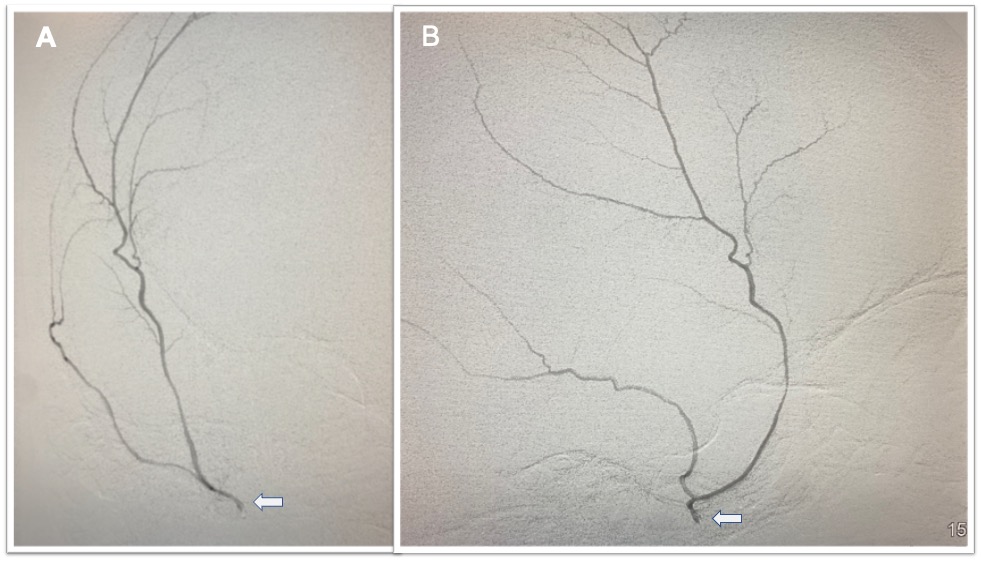

Middle Meningeal Artery Embolization – This procedure is performed in an endovascular intervention suite with the patient under sedation. The endovascular surgeon uses minimally invasive technique to enter the blood vessels in the arm or leg, advances small tubes through the arteries under x-ray guidance and navigates them to the middle meningeal artery on the side of the chronic subdural hematoma. The middle meningeal artery is located on the underside of the skull in the dura matter but also provides blood supply to the abnormal membranes that surround the hematoma and contribute to hematoma growth (see Figure 2). Under fluoroscopic guidance (low dose continuous x-rays), the surgeon delivers a specially made glue or small particles through the small tube and permanently blocks the middle meningeal artery. After the procedure, the tubes are removed and the small puncture site in the arm or leg artery is closed. In the weeks following the procedure, there is reduced bleeding from the subdural hematoma membranes and the hematoma collection slowly shrinks in size and often goes away completely over the course of several months (see Figure 3).

Figure 2. A) Anterior to posterior (front to back) view of the right side of the head with a microcatheter (tiny tube) in the right Middle Meningeal Artery (arrow) injecting contrast dye into the vessel which branches along the underside of the skull. B) The lateral view of the same microcatheter (arrow) injecting contrast dye filling the right Middle Meningeal Artery. This vessel was occluded to treat a chronic subdural hematoma.